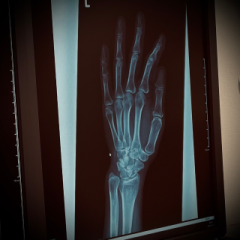

レントゲン写真。。

ぁ、

骨、

カッコぃぃ。。♡

我ながら、

イイ骨だゎ。。(笑)

骨に、

異常はなぃらしぃ。。

ヨカッタ。。